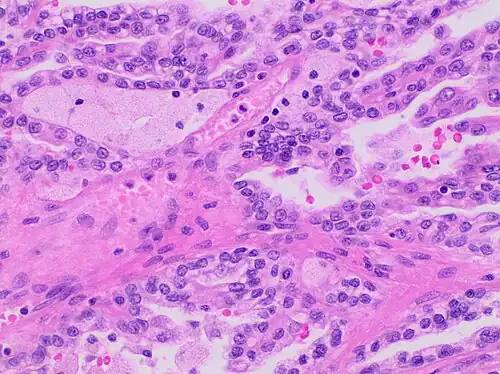

Type 1 PRCC, this case being more compact at right.

Type 2 Papillary renal cell carcinoma

Accounting for 25% of PRCCs, type 2 PRCC is the pathological subtype that is most commonly associated with hereditary leiomyomatosis and renal cell carcinoma (HLRCC) syndrome.[14][15] When compared to type 1, it shows more variation in protein expression mostly by loss of CK7.[16] In a gross examination, it shows papillae covered by large cells abundant in eosinophilic cytoplasm.[18] Its large spherical nuclei on papillary cores are arranged in a pseudo-stratified manner.[16] Unlike type 1 PRCC, foamy macrophages and psammoma bodies are less common in case of type 2.[15] The majority of type 2 PRCC has high Fuhrman grade nuclei with prominent nucleoli.[16]